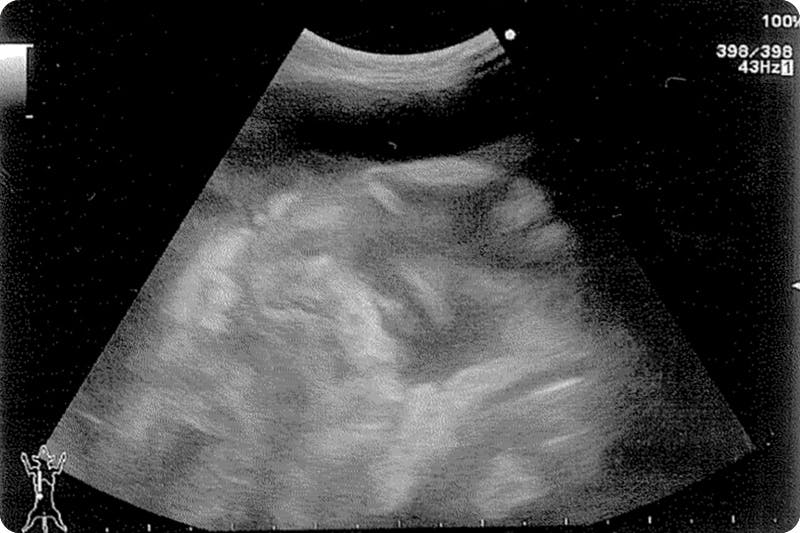

毎日病院で点滴を受け血液検査、レントゲン、エコー、注射を繰り返す日々。

キティの場合ウェットタイプです。

腹水が貯まりパンパンになりました。

9月7日(月) 病院Aにてレントゲン、エコー